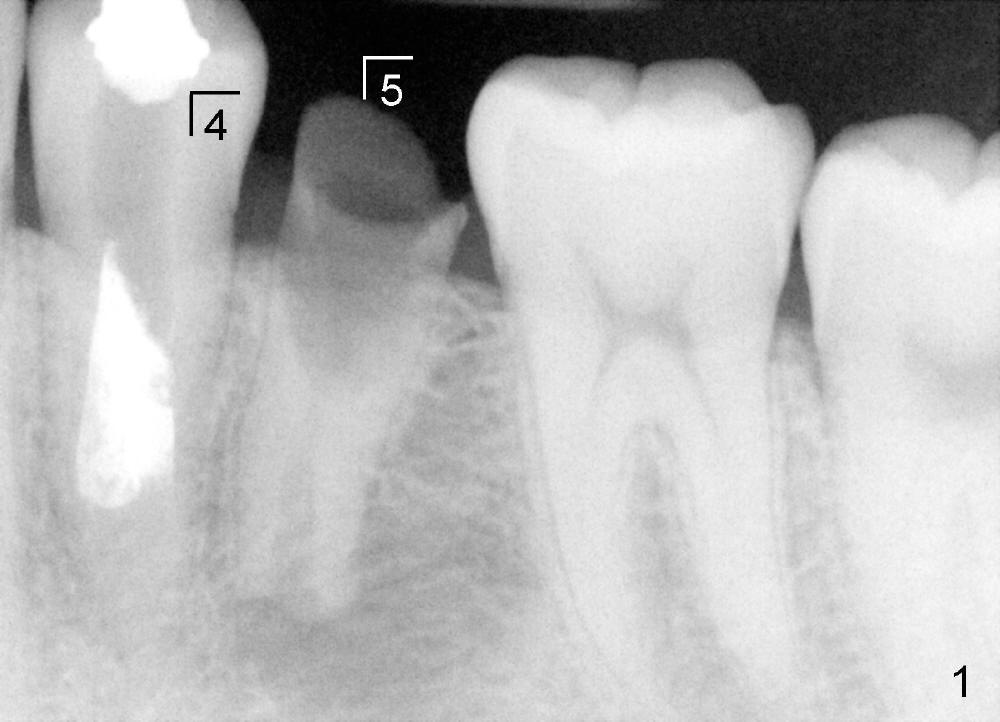

五年前,小许二十出头,四个下颌双尖牙中央牙尖畸形,左下第二双尖牙(图一:5)好像没有症状,但挺难保留,拔除后三个月植牙(delayed vs. immediate,这治疗(delayed implantation)合适吗?),图二是牙冠(C)戴上后半年拍摄的,A:基牙,I:Bicon植牙(5x8 mm,太短吗?)。虽然第一双尖牙也没有症状(图一:4),植牙前,重做根管治疗(图二:R,过分治疗吗?),使用flowable(*)和packabe(B)树脂关闭根管治疗开口,选择不做牙冠(治疗不足?)。